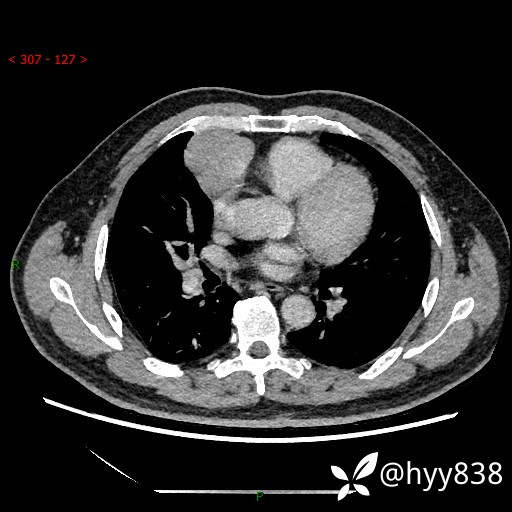

动脉期+静脉期